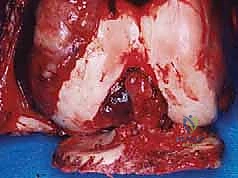

الحالة الأولى: إنقاذ ركبة رياضي شاب

شاب يبلغ من العمر 19 عاماً عانى من ألم مستمر في الركبة وتورم لم يستجب للمسكنات. بعد الفحص السريري الدقيق وإجراء الرنين المغناطيسي، اشتبه الأستاذ الدكتور محمد هطيف بوجود ورم. تم إجراء خزعة إبرة أساسية دقيقة جداً. أظهرت النتائج وجود "ساركوما عظمية" في مراحلها الأولى. بفضل الخزعة الدقيقة التي لم تلوث الأنسجة المحيطة، تمكن الدكتور هطيف لاحقاً من استئصال الورم بالكامل وتركيب مفصل صناعي خاص بالأورام، مما أنقذ ساق الشاب من البتر ومكنه من العودة للمشي بشكل طبيعي.

- إذا كان الورم حميداً: قد يكتفي بالمراقبة الدورية، أو يوصي باستئصال بسيط إذا كان الورم يسبب ألماً أو يهدد بكسر العظم.

- إذا كان الورم خبيثاً (ساركوما): يتم وضع خطة علاجية شاملة (Multidisciplinary approach) قد تتضمن العلاج الكيميائي، العلاج الإشعاعي، والجراحة الكبرى لاستئصال الورم مع الحفاظ على الطرف (Limb Salvage Surgery).